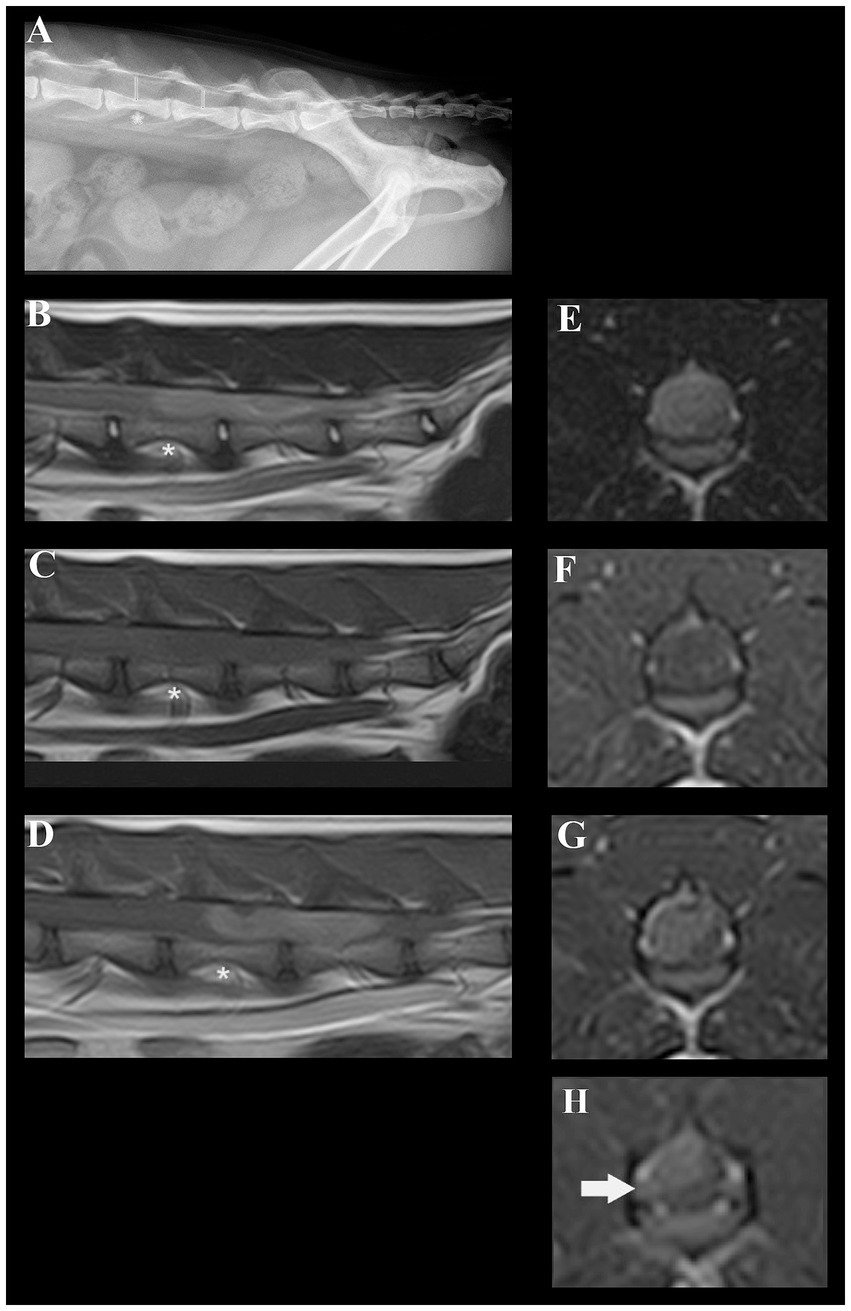

Neuroanatomical localization was to the L4-caudal spinal cord segments, nerve roots, and/or spinal nerves worse on the right side. Our differential diagnoses included predominantly degenerative (intervertebral disc degeneration and herniation), anomalous, neoplastic, and inflammatory processes. Lateral radiographs (acquired by the referring veterinarian) revealed a subjectively increased dorsoventral height of the spinal canal centered at the level of the L5 and L6 vertebrae (Figure 1A). The cat was anesthetized and positioned in dorsal recumbency for a magnetic resonance imaging (MRI) study of the thoracolumbar spinal cord (1.5 T Canon Vantage Elan). The following sequences were performed: sagittal plane T2W, sagittal plane T1W, sagittal plane short-tau inversion recovery (STIR), dorsal plane STIR, transverse plane T2W, transverse plane T1W, transverse plane T2* GRE, sagittal plane T1W post-contrast, transverse plane T1W post-contrast, and sagittal plane 3D T1W magnetization prepared—rapid gradient echo (MPRAGE). MRI revealed a large, moderately well-defined and slightly lobulated space-occupying lesion, extending from the mid-body of L5 to the caudal aspect of L6 (Figures 1B–G). The lesion originated from the right side and occupied or compressed most of the spinal cord parenchyma. At the level of L6-7, it appeared to extend and affect the right ventral nerve root (Figure 1H). The caudal aspect of the lesion was ill-defined and may cause mass effect on the cauda equine nerves. The lesion was slightly heterogeneous, mainly hyperintense on T2-weighted (T2W) and STIR when compared to the spinal cord, mildly hypointense on T1W images, and had mild to moderate slightly heterogeneous contrast enhancement. Small areas of hypointensity/signal void within the lesion were appreciated from the T2* sequence. No golf tee sign or dural tail sign was conclusively observed. The large volume of the mass prohibited conclusions on the exact localization of the mass lesion (i.e., intradural, intradural/extramedullary, or extradural) but an intradural and possibly at least partially intramedullary localization was suspected. Despite the size of the mass, no surrounding spinal cord oedema or dilation of the central canal were noted.

Figure 1. Radiographic and magnetic resonance images of a cat diagnosed with a presumed embryonal tumor affecting the spinal cord. (A) Lateral radiograph of the vertebral column. The dorsoventral spinal canal height is subjectively increased centered at the level of the L5 and L6 vertebrae (red lines, red asterisk at the level of L5). (B) Sagittal plane T2W MRI; a slightly heterogeneous, mainly hyperintense space occupying lesion is present in the spinal canal. Red asterisk at the level of L5. (C) Sagittal plane T1W MRI; a mildly hypointense space occupying lesion is present in the spinal canal. Red asterisk at the level of L5. (D) Sagittal plane T1W + contrast; moderately heterogeneous contrast-enhancement of the lesion can be noted. Red asterisk at the level of L5. (E) Transverse plane T2W at the level of L5; the moderately well-defined right sided mass lesion can be identified. (F) Transverse plane T1W at the level of L5; the lesion is mildly hypointense. (G) Transverse plane T1W + contrast at the level of L5; moderately heterogenous enhancement of the lesion can be identified. (H) Contrast-enhancement and mild swelling of the right-sided L6 nerve root can be appreciated.